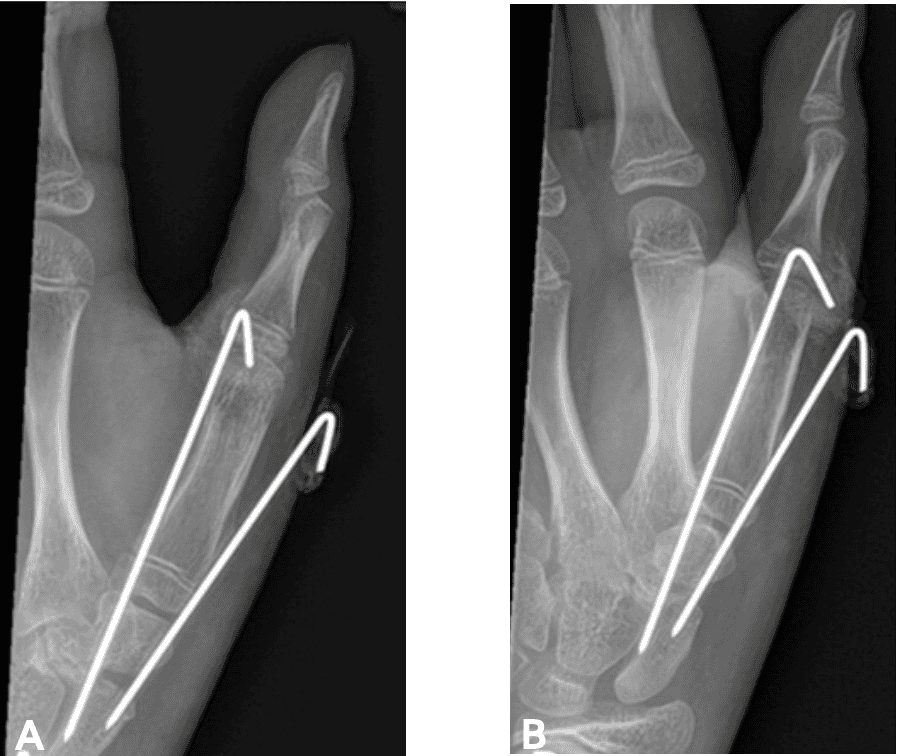

Figures 1-3 below descript the patient initial medical condition and subsequent surgical procedures prior to use of OSSIOfiber® implants

Screenshot 2026 01 20 At 2.48.03 Pm Ossio – Naturally Transformative Bone Healing

Figure 2: Post-operative X-rays taken January 2023,following first surgery, using metal K-wires.

Oblique thumb view [A] and Lateral thumb view [B]